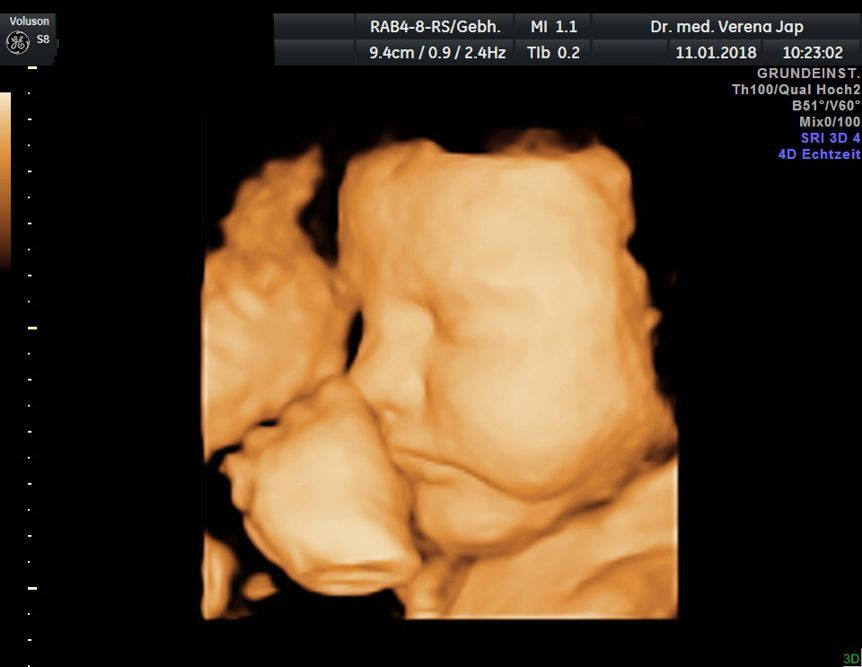

Hier wollen wir Ihnen einen Einblick in die Praxisräumlichkeiten geben. Die Untersuchung findet in ruhiger Atmosphäre in einem hellen und freundlichen Raum statt. Gleichzeitig bieten wir Ihnen eine moderne und zeitgemäße Ausstattung mit Ultraschall auf höchstem technischen Niveau, Phasenkontrastmikroskopie und Videokolposkopie.